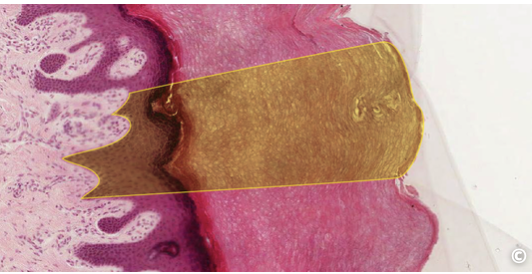

<p>identify structure</p>

identify structure

thin skin; stratum corneum; keratinized stratified squamousepithelium